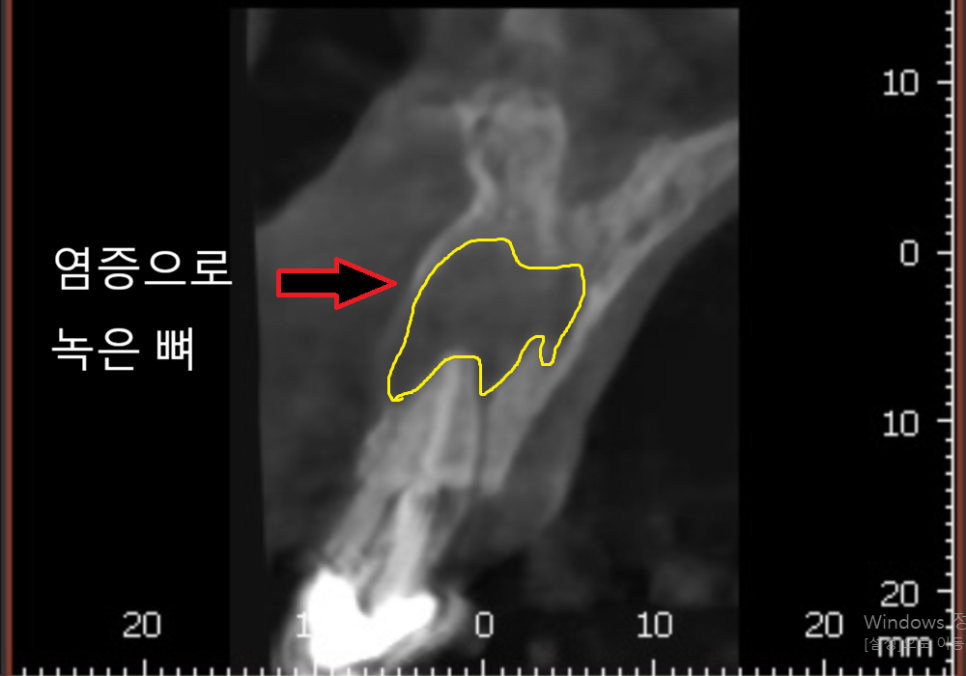

CT상에서도 뿌리 염증이 꽤 진행되어 있었지만,

260220

치아 뿌리 끝 염증은

통증 없이 조용히 뼈를 녹이는 경우가 많거든요.

그로 인해 주변 잇몸뼈가 녹아내려

결국 정말 치아를 뽑아야만 하는

상황에 이르게 됩니다.